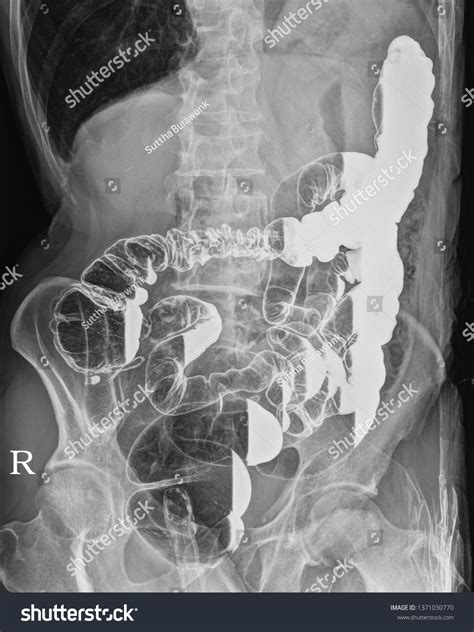

• Abdominal Imaging: It helps in shifting bowel loops, which can obscure the visualization of the gallbladder, kidneys, or other retroperitoneal structures.

When performing imaging in the Right Lateral Decubitus position, technicians must be precise with beam angulation and patient orientation. If the goal is to detect a pleural effusion, the patient is placed so that the side being examined is the "down" side. This allows the fluid to gravitate to the dependent portion of the thoracic cavity, where it is more easily identified against the chest wall. Conversely, if searching for free intraperitoneal air (pneumoperitoneum), the patient is often placed so that the potential air space is at the highest point.

Mastering the Right Lateral Decubitus requires recognizing how gravity interacts with specific pathologies. For example, during an ultrasound-guided procedure, this position might be used to displace the liver or gallbladder into a more favorable position for needle entry. The clinician must have a clear understanding of the patient's anatomy to maximize the efficacy of this position. If the positioning is incorrect by even a few degrees, the target organ might move behind bony structures like the ribs, making the procedure significantly more difficult or even impossible.